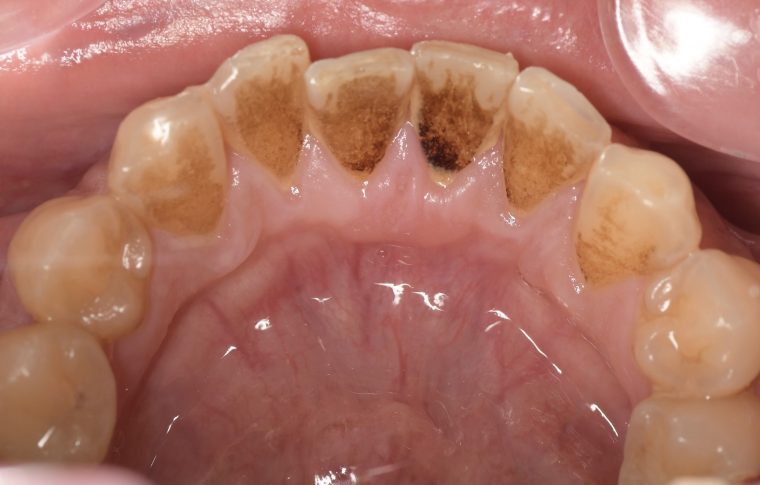

CASE 4

| 年齢・性別 | 52歳・女性 |

|---|---|

| 主訴 | クリーニングしたい |

| 治療内容 | スケーリング・PMTC |

| 治療期間 | 60分 |

| 治療費 | 約7,000円 |

| リスク・副作用 | 知覚過敏、歯肉退縮 |

| 治療方針 | 歯石とステインを除去して、今後は定期検診でのクリーニングと併せてガムピーリングやホワイトニングを行います。 |

| 担当者所見 | 歯肉の色素沈着が目立つため、ガムピーリングを行いながらホワイトニングを行うことをおすすめします。 |